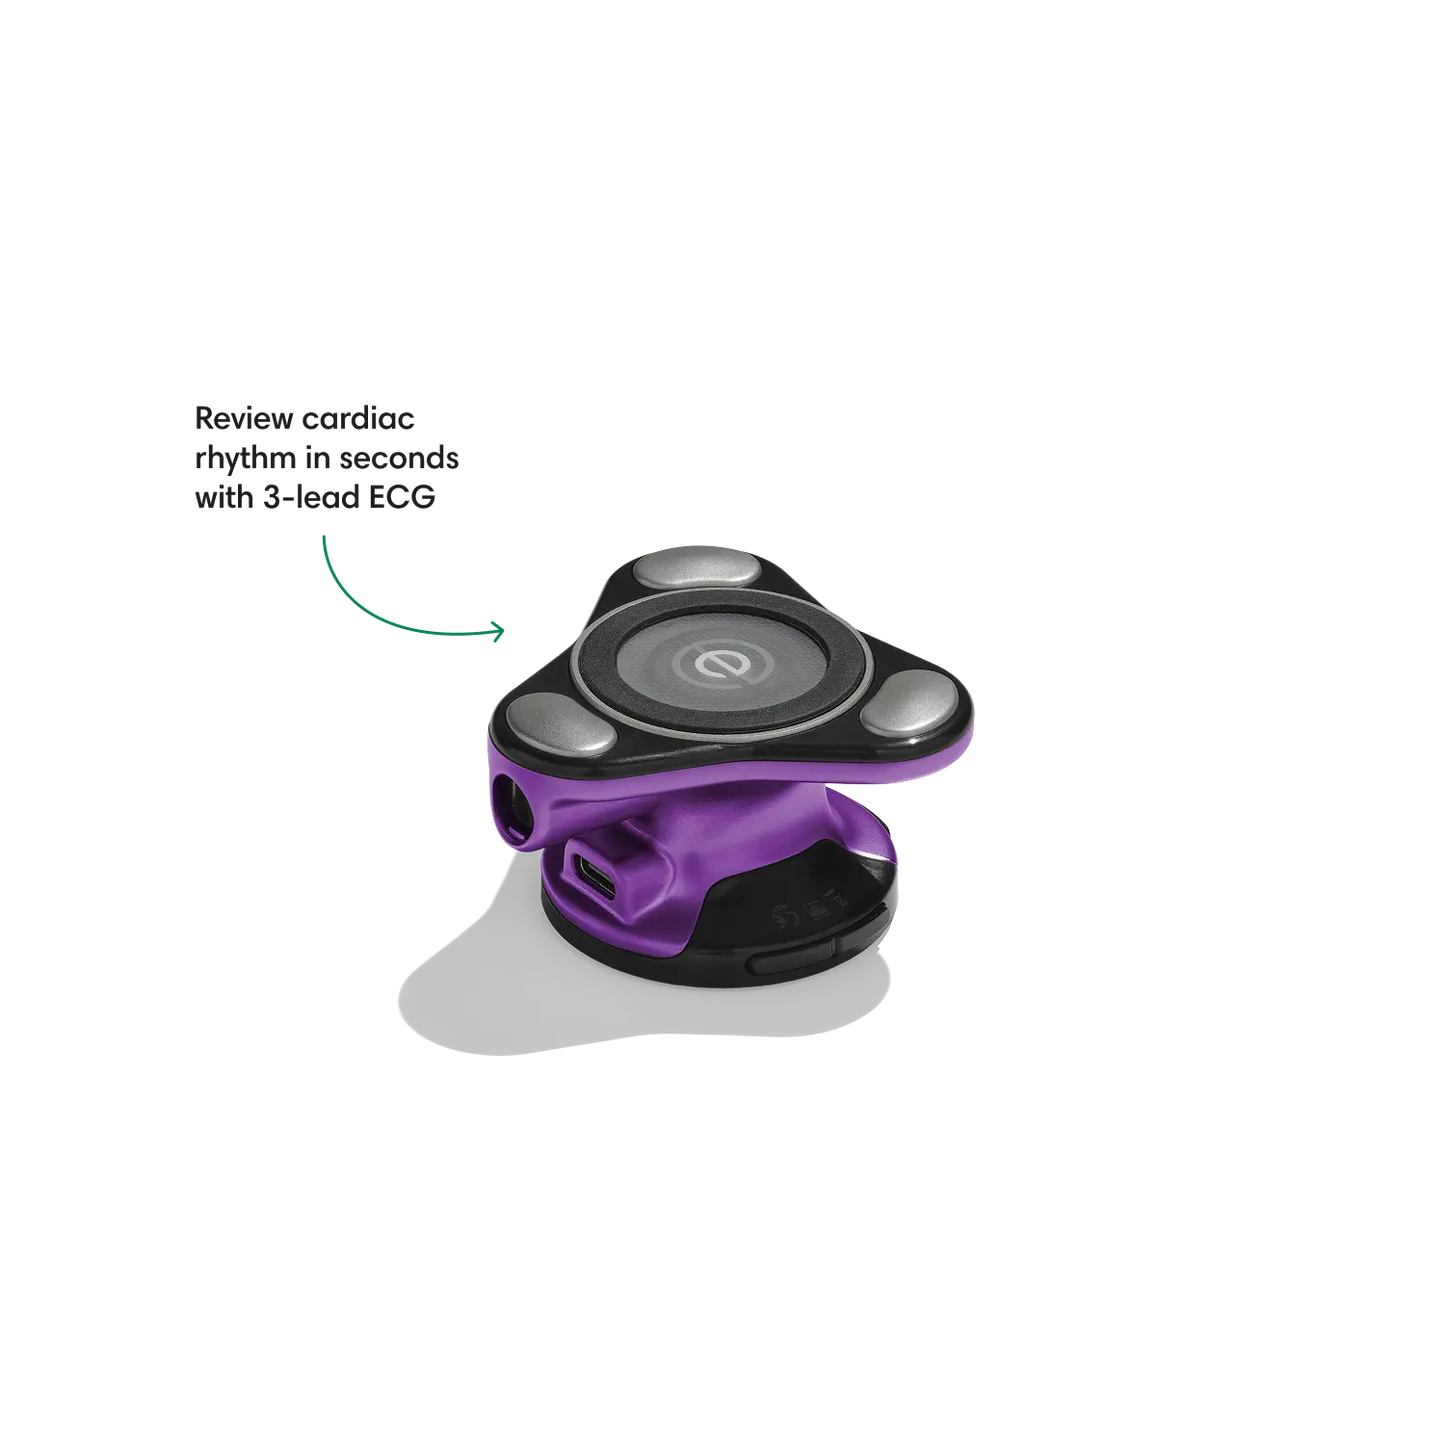

Go beyond sound alone.

For the first time ever, measure heart rate, visualize 3-lead ECG, and see detection results — right on a built-in, full-color display.

Yes! Make your stethoscope uniquely yours with custom engraving, and colorful accessories like ear tips and chestpiece covers.